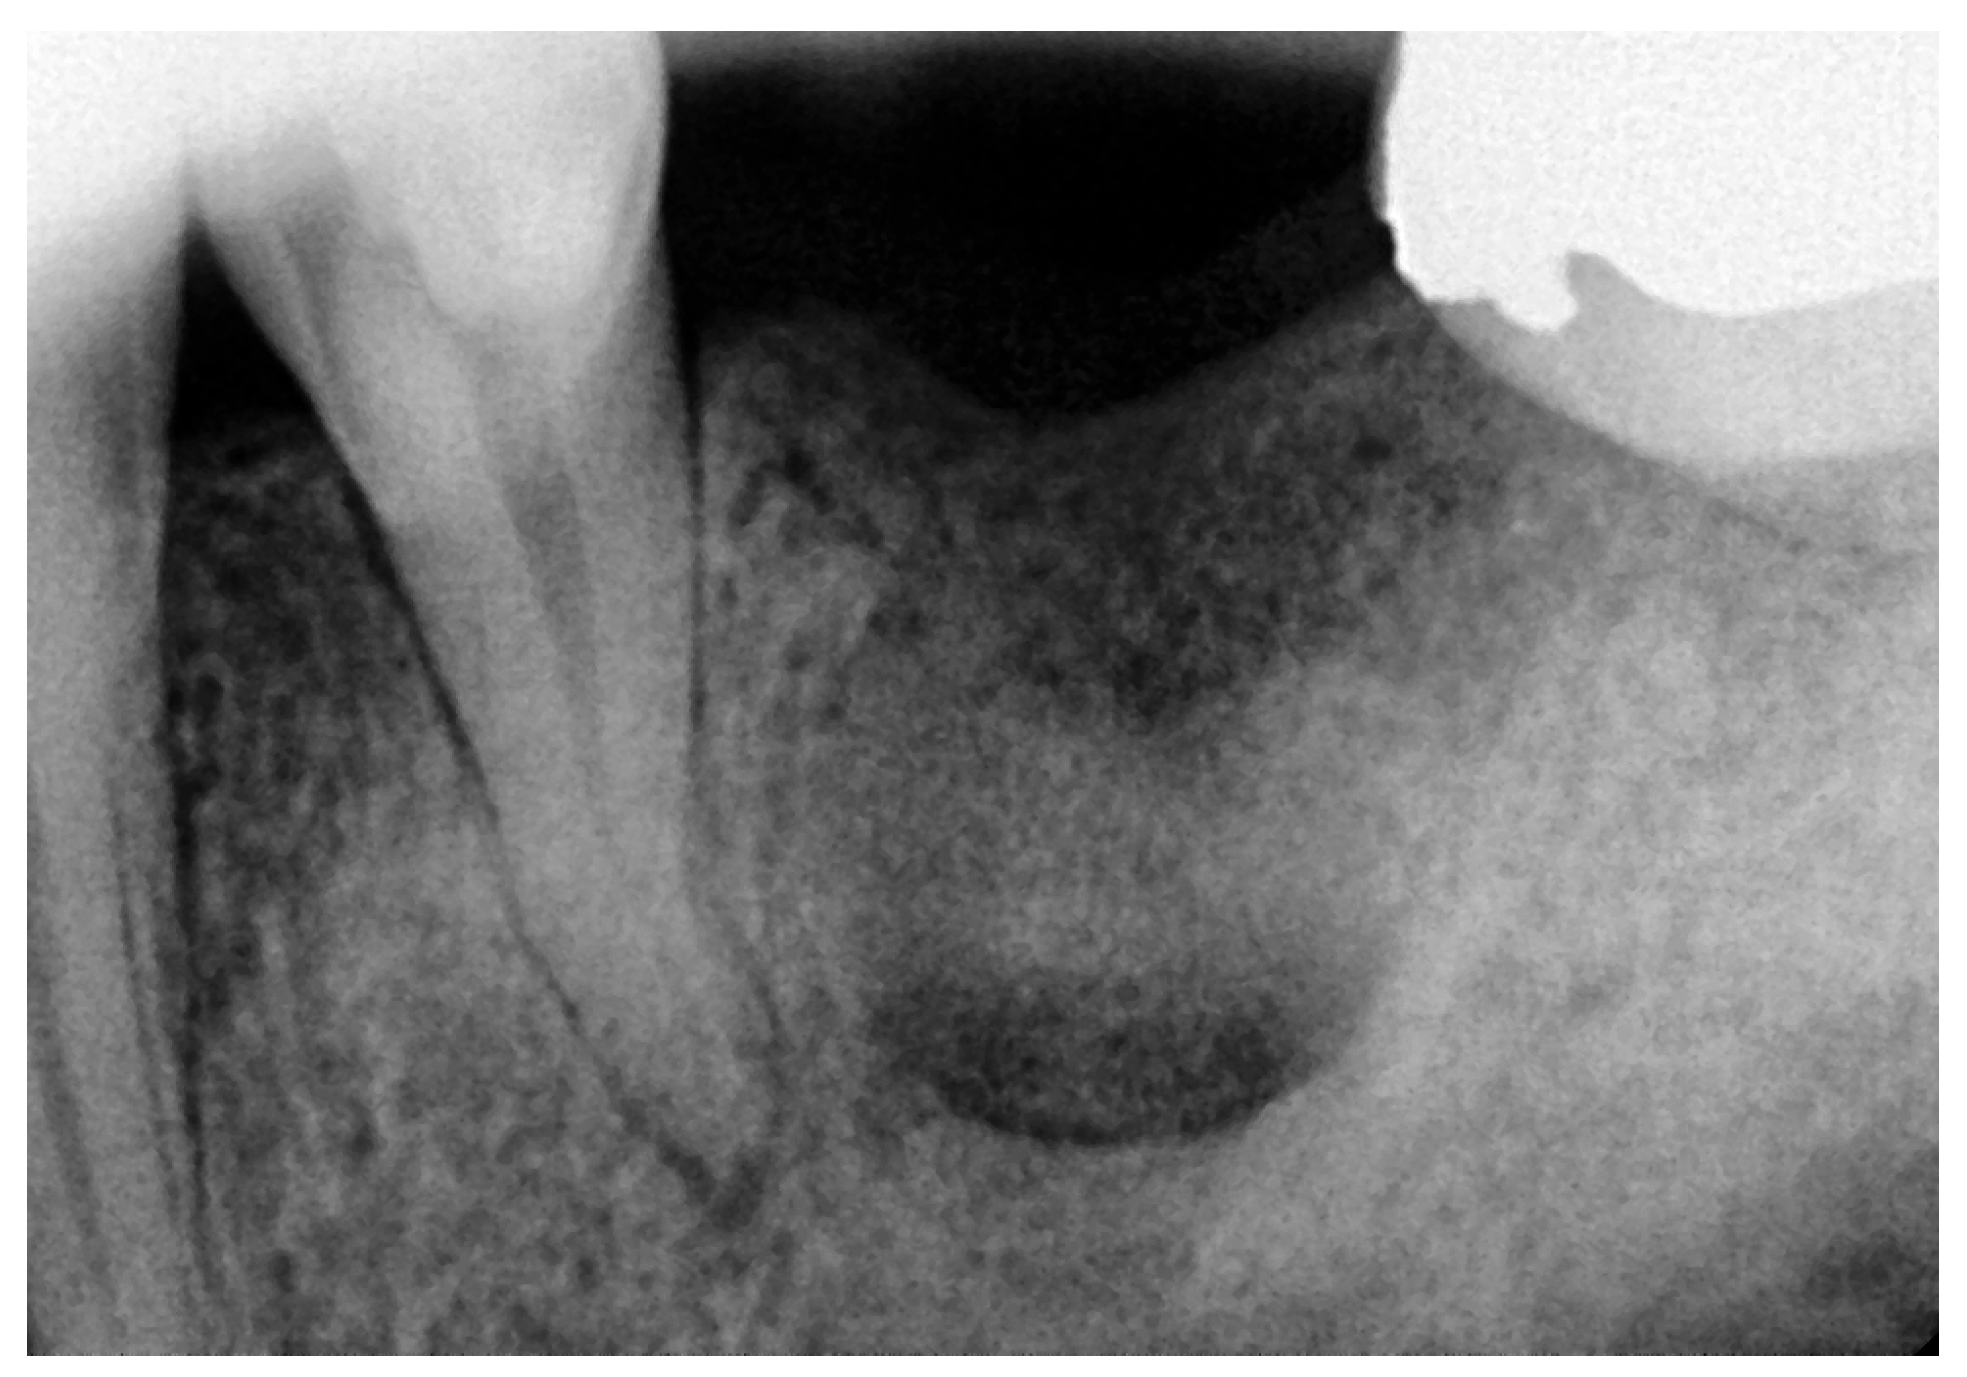

2.1. Initial Visit, Radiographic Evaluation and Diagnosis

2.2. Surgical Intervention